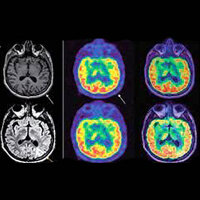

La neuropsicología ha tenido un crecimiento notorio, se considera el área con mayor desarrollo dentro de la psicología y dentro de las neurociencias en general. Encontramos avances como: Surgimiento de las imágenes cerebrales, utilización de pruebas estandarizadas en el diagnóstico, desarrollo del área de la rehabilitación neuropsicológica, profesionalización de la neuropsicología, aumento en el número de publicaciones, integración conceptual, ampliación del campo de trabajo. pág. 26

Se fortalece la investigación con el empleo de imágenes noya anatómicas sino funcionales, en particular la resonancia magnética funcional y la tomografía por emisión de positrones, que han permitido visualizar la actividad cerebral durante la realización de diferentes tareas cognoscitiva como, hablar, leer etc. pág. 27